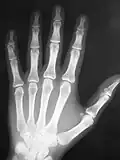

A typical image is shown in Figure 3.10. It can be seen that bone has a brighter shade of grey than that of the enveloping tissue and is brighter still than the surrounding air. This is the conventional method of displaying a radiograph such that higher photon attenuation is encoded as a brighter shade of grey.